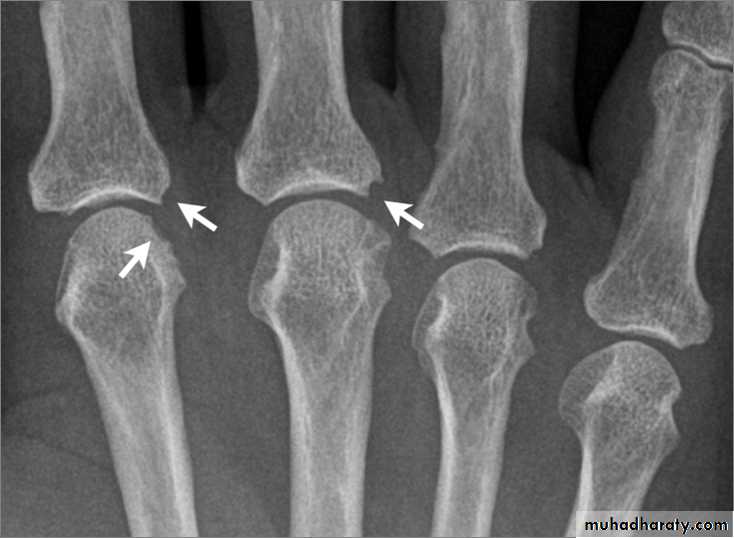

Рентгеновские снимки остеосклероза костной ткани